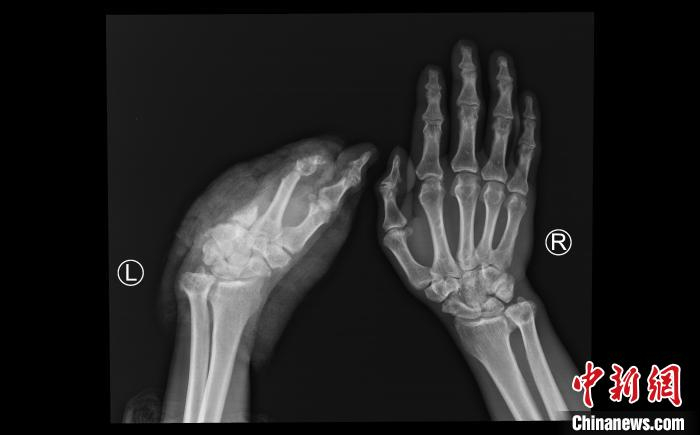

中新网成都8月26日电 (记者 王鹏)记者26日从四川省人民医院获悉,该医院骨科团队近日完成一例超高难度断掌再植手术——患者手掌因车祸离断超24小时,最终断掌被成功再植。目前经过术后两周的康复,患者准备出院。

该患者为55岁男性,西藏昌都人。8月9日下午,患者因车祸伤导致左手掌完全离断,因当地医院无再植医疗条件,经过初步处理后,采用疫苗冷链箱保存离断肢体,搭乘飞机于8月10日下午到四川省人民医院骨科急诊入院。

经过积极的术前准备,在麻醉手术中心等相关科室的支持下,肖成伟团队很快开始了急诊再植手术。经过显微镜下长达6个半小时的奋战,一共吻合重建了3根动脉,6根静脉,5根神经,14根肌腱。8月11日凌晨2点,患者离断肢体恢复供血,再植手术获得初步成功。

术后一周后,再植肢体安全度过了术后发生血管危象的可能。目前再植肢体完全存活,其他功能也在逐步恢复中。肖成伟介绍,康复后患者虽然不能进行精细动作,但一般的生活自理没问题。